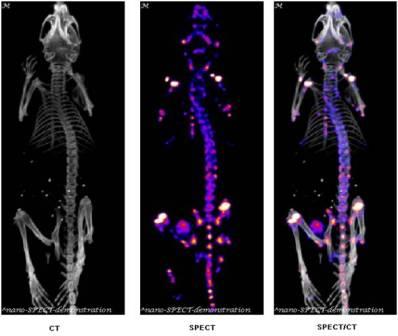

SPECT/CT Images

111In labeled oligomer |

188Re labeled oligomer |

99mTc labeled oligomer |

99mTc labeled peptide |

SPECT/CT fusion of 99mTc-MDP Bone Scan